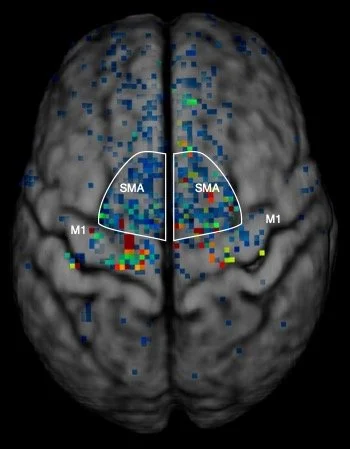

The Imaging working group is focused on exploring the use of advanced imaging technologies to gain further insights into the underlying mechanisms of cerebellar mutism syndrome. By utilizing advanced magnetic resonance and functional imaging techniques, this group aims to identify structural and functional abnormalities in the cerebellum that may contribute to this condition. Their research may unveil crucial information on the pathophysiology of cerebellar mutism syndrome and guide clinicians in developing more targeted treatment interventions.